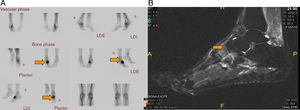

(A) Coronal magnetic resonance imaging (MRI), with fat saturation, showing bone edema in diaphysis of the second metatarsal of left foot, and in neighboring soft tissue. (B) Sagittal MRI of left foot in short tau inversion recovery (STIR) sequence showing bone edema in diaphysis of the second metatarsal, and in neighboring soft tissue. (C) Plain radiography showing the image of the fracture callus in the diaphysis of the second metatarsal of left foot.

We present the case of a male HIV-positive patient (diagnosed in 1999), who began antiretroviral therapy with the following regimen. From September 1999 to November of the same year, he took stavudine (d4T) plus didanosine (ddi) and nelfinavir. In November, he changed to zidovudine (AZT) plus lamivudine (3TC) and nevirapine, which he maintains until July 2008, when he began with emtricitabine, plus tenofovir, as well as nevirapine, until the present time. In 2011, he came to the rheumatology clinic with a 2-month history of pain in the dorsum of his right foot, with no previous injury. He underwent bone scintigraphy using Tc-99m, which revealed a severe trauma in the naviculocuneiform region of the right tarsus and a focal lesion of the third metatarsal bone of the right foot, suggestive of a stress fracture (last densitometry, T-score in femur: −2.3 standard deviations [SD]; T-score in spine: −2.4 SD) (Fig. 1A). Magnetic resonance imaging (MRI) showed a clear signal alteration in midfoot, which was manifested as a somewhat lower signal intensity in T1 and an increase in short tau inversion recovery (STIR) sequences, with a discreetly higher signal intensity at the base of the third metatarsal bone. The suggested diagnosis was a stress fracture of right midfoot affecting the naviculocuneiform joint, at the cuboid and third metatarsal bone of the right foot (Fig. 1B). He was treated with nonsteroidal anti-inflammatory drugs (NSAID) and rest. Three months later, the fracture had healed without side effects. In 2012, after an overexertion, the patient presented with mechanical pain in the region of the metatarsus of the left foot. As another stress fracture was suspected, he underwent MRI, which revealed bone edema in the diaphysis of the second metatarsal bone, and in the neighboring soft tissue, consistent with a stress fracture of the second metatarsal bone of the left foot (Fig. 2A and B). He was treated with rest and conservative measures and, the symptoms disappeared in 2 months (plain radiography showed an image of a fracture callus in the diaphysis of the second metatarsal of the left foot (Fig. 2C). On the 30th of January of 2014, the patient returned to the rheumatology clinic, with an increase in the volume of right ankle after another overexertion (a simple walk). Given the possibility of another fracture, he was studied by MRI, which showed a linear image at the level of the talar head, adjacent to the talonavicular joint. He also had a subchondral lesion at the level of the talus (talonavicular joint) with an irregular increase in the talus (Fig. 3A and B).